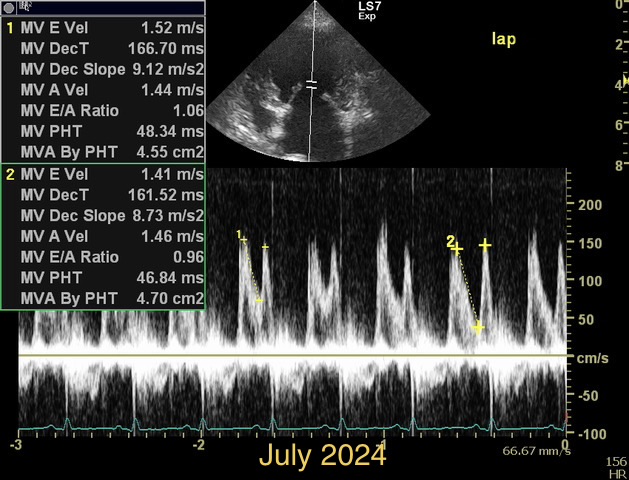

How would you diff b/w reverse remodelling and MV stenosis. Presented at recheck with mod severe pulmonary HT. Smll dog treated for chronic MVD stage C. US= LV under loading, FS > 50%, LAE remains significant. M e-vel is consistently 1.5m/s or higher but dec. time and press half time appear normal. E:A ratio around 1. Would LAE remain with aggressive medical Tx for MVD due to LA remodelling, LA compliance ,chronicity of MVD and ongoing reg. vol. compared to potential for LV to undergo reverse remodelling with Tx. Is stenosis seen much in min breed old dogs? Ls7 vid=2024. Tks!!

I see MS at all ages, because it is frequently missed in young dogs. But this case is not a MS. It is diagnosed as a combination of 2D-echo findings and the typical Minflow profile (E-wave very high frequently >2 m/s) confluent with A-wave. See image and video.